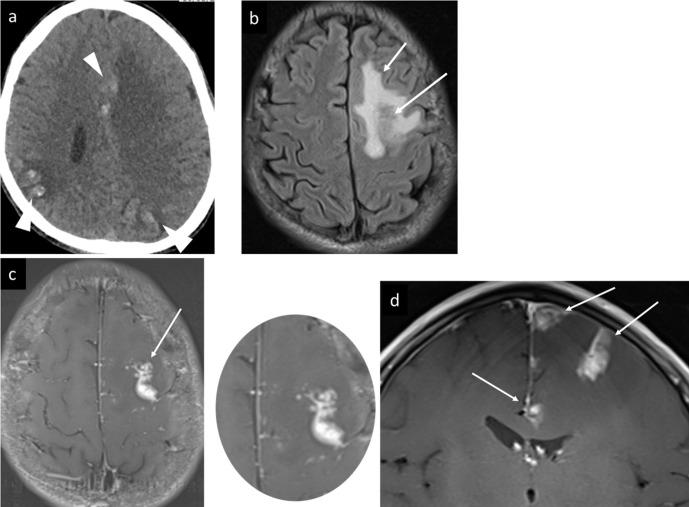

We describe three cases of neuroschistosomiasis, two cases with cerebral schistosomiasis due to , with multiple pseudotumoral lesions presented with seizures and hemiparesis respectively, and a spinal cord conus medullaris schistosomiasis due to presented with conus medullaris syndrome. In the two cases with cerebral schistosomiasis imaging with CT revealed multiple areas of brain edema, and gyriform calcifications in both cerebral hemispheres, which suggested cerebral parasitemia, chronic venous hypertension, multifocal cerebral vascular malformation, or a forme fruste Sturge Weber syndrome. Further MRI revealed corresponding blooming, T2W (weighted) -FLAIR (fluid attenuated inversion recovery) ibright signal intensity and enhancing lesions. In the third case with spinal cord involvement MRI revealed signal abnormality on T1W and T2W images with patchy and punctate post i.v. contrast enhancement of the conus medullaris. Excision biopsy and histopathological examination were undertaken for the first brain case and spinal cord case and showed multiple schistosomal granulomas in different evolution phases. In the second brain case, the diagnosis was suggested based on our experience with prior cases, positive laboratory tests, and urinary bladder wall biopsy. Neuroschistosomiasis must be considered in the differential diagnosis of multiple cerebral calcifications, and multiple nodular and linear like lesions with characteristic arborized enhancement pattern, especially for patients coming from endemic areas for Schistosomiasis.

我们描述了三例神经血吸虫病病例,两例为脑血吸虫病,分别由[具体病因未给出]引起,表现为多发性假瘤样病变,分别伴有癫痫发作和偏瘫,另一例为脊髓圆锥血吸虫病,由[具体病因未给出]引起,表现为脊髓圆锥综合征。在两例脑血吸虫病病例中,CT成像显示多个脑水肿区域,双侧大脑半球有脑回状钙化,提示脑寄生虫血症、慢性静脉高压、多灶性脑血管畸形或顿挫型斯特奇-韦伯综合征。进一步的MRI显示相应的磁敏感伪影、T2加权-液体衰减反转恢复序列(T2W-FLAIR)高信号强度和强化病变。在第三例脊髓受累病例中,MRI显示T1加权和T2加权图像上信号异常,脊髓圆锥静脉注射造影剂后有斑片状和点状强化。对第一例脑病例和脊髓病例进行了切除活检和组织病理学检查,结果显示不同演变阶段的多个血吸虫肉芽肿。在第二例脑病例中,根据我们既往病例的经验、阳性实验室检查结果和膀胱壁活检做出诊断。在鉴别诊断多发性脑钙化以及具有特征性树枝状强化模式的多个结节状和线状病变时,必须考虑神经血吸虫病,特别是对于来自血吸虫病流行地区的患者。